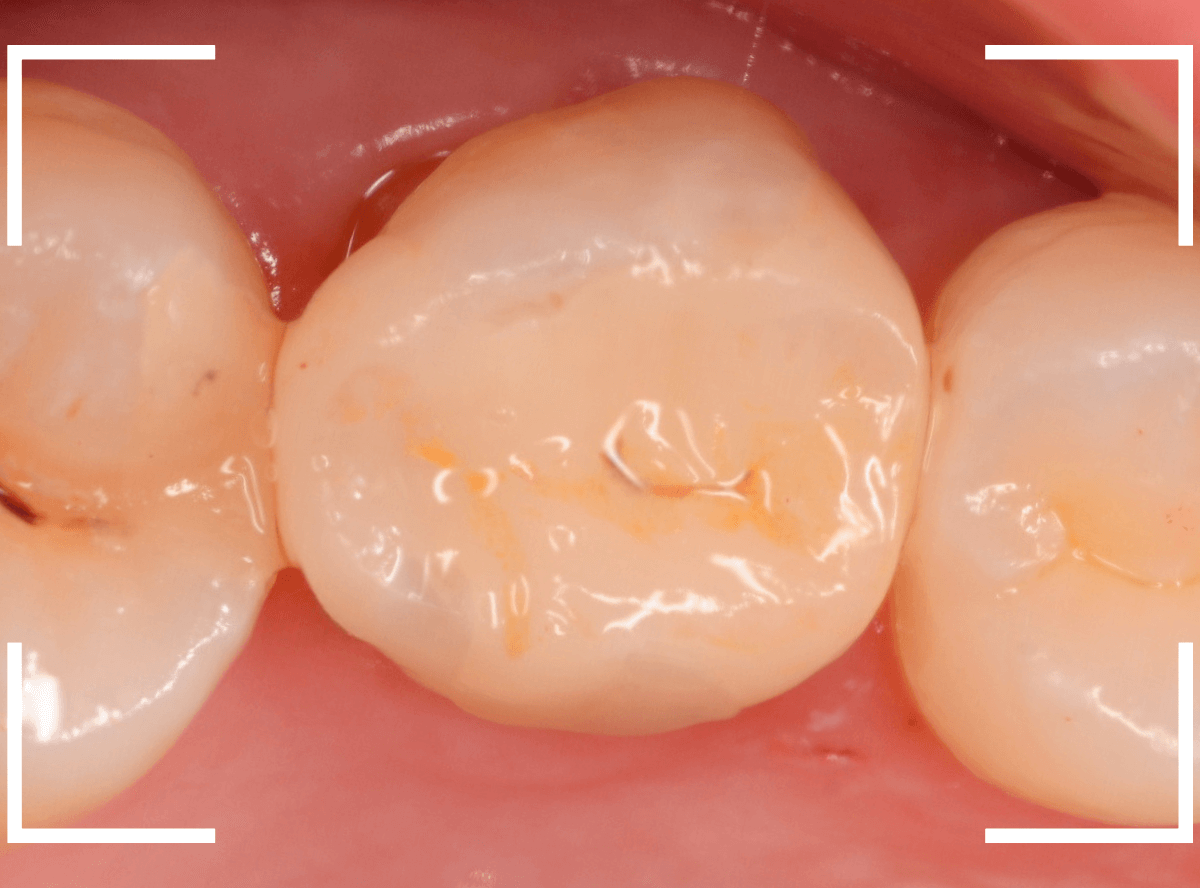

治療後の状態です。

自然な仕上がりで、患者さんにもご満足いただけました。